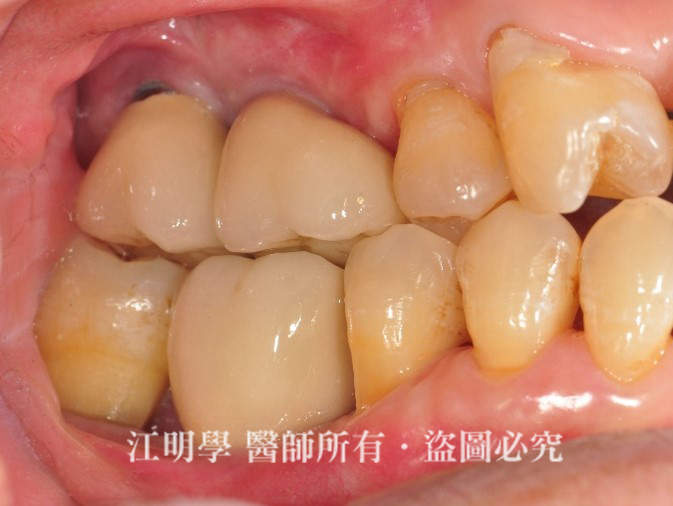

因為右側缺牙沒有處理,長期過度使用左側單邊咀嚼食物,造成咬合重心偏移、咬合面嚴重耗損,拍照時會發現臉型不對稱、好像歪了一邊,就是長期只靠單邊咀嚼導致的。

治療後:植牙將缺牙補齊,重建口腔咬合。

牙齒獲得支撐力,空隙逐漸合起來。